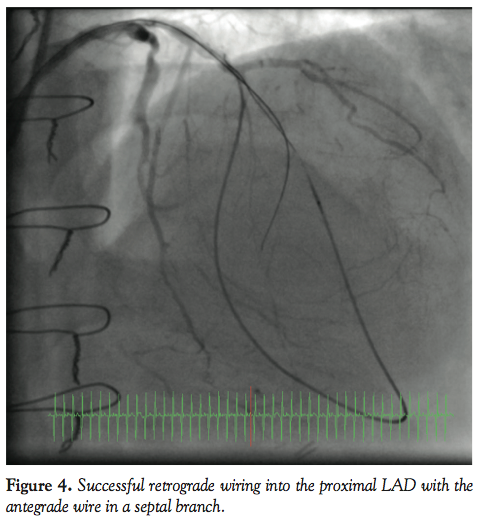

Angiogram showed the LAD occlusion in the mid course with a septal collateral filling the distal LAD retrogradely (Figure 1). An angioplasty Sion wire with a Corsair catheter (Asahi Intecc Co Ltd) was introduced into the LAD and the septal collateral and distal LAD retrogradely and a Confianza Pro12 (Asahi Intecc) antegradely through the proximal occlusion cap (Figure 2). The anterograde wire was passed into a septal branch, which gave a road map for the retrograde wire. The retrograde Sion wire was exchanged for a Pilot 200 wire (Abbott) which was navigated retrogradely (Figure 3) and crossed the proximal occlusion cap followed by the Corsair catheter (Figure 4). Following that, a 300 cm RG3

wire (Asahi Intecc) was externalized and the Corsair catheter removed with initial 1.5 balloon dilatation performed retrogradely (Figure 5). Further 2.0 balloon dilatation was performed antegradely and subsequently 2 Promus Element DESs (Boston Scientific) were deployed and the distal LAD was treated with plain old balloon angioplasty with the 2.0 balloon, with excellent final results (Figure 6). The patient tolerated the procedure well with no complications and was monitored on the ward and allowed home in a stable condition.